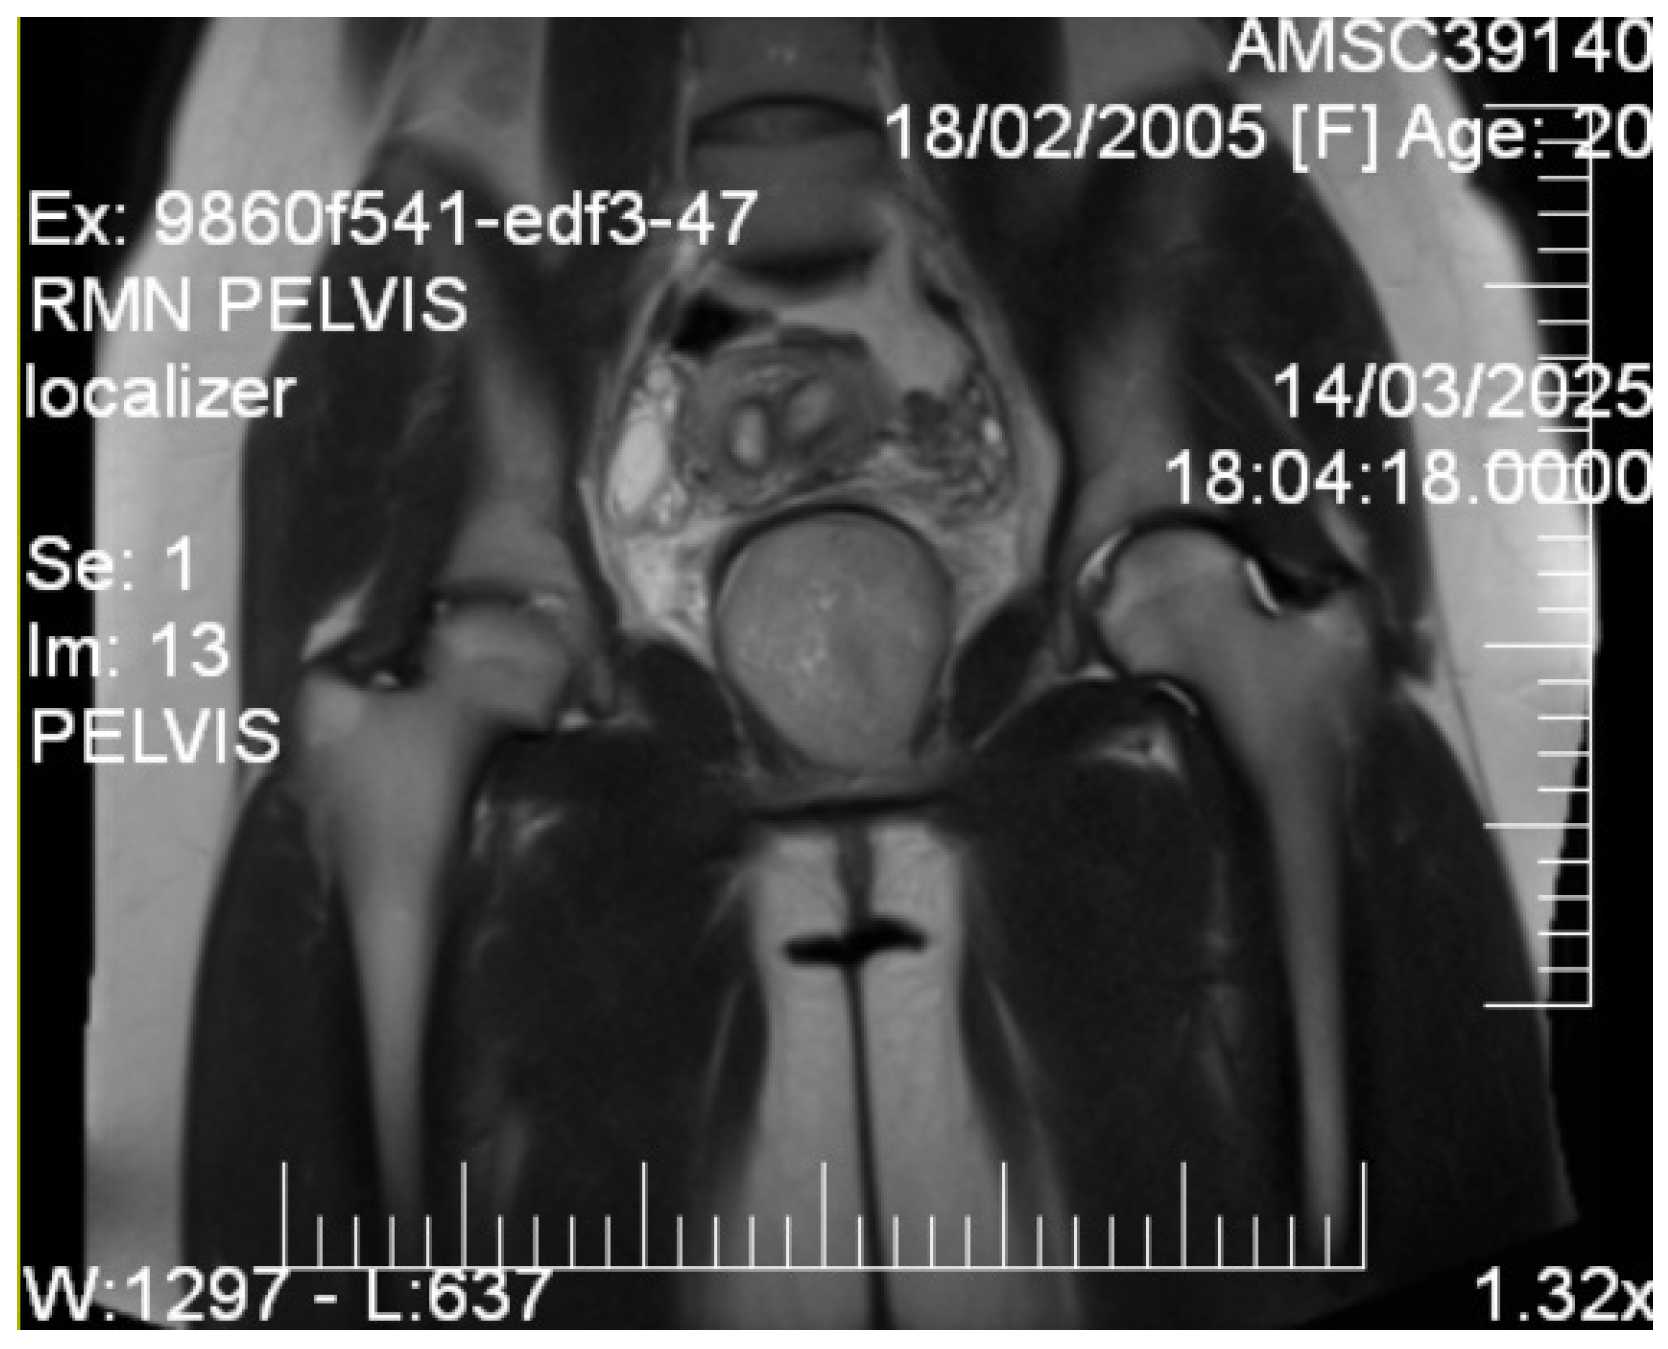

Given the patient’s young age and solid mass characteristics raising concern about malignancy, comprehensive magnetic resonance imaging (MRI) was performed using a 1.5-Tesla scanner with multiplanar sequences (General Electric, Cluj-Napoca, Romania). The MRI demonstrated signal intensity patterns highly suggestive of leiomyoma: isointense to muscle on T1-weighted imaging, markedly hypointense on T2-weighted imaging (characteristic of leiomyoma due to high fibrous content), restricted diffusion with high ADC values of 0.9 × 10−3 mm2/s (b-values: 0, 1000 s/mm2) consistent with benign leiomyoma, and homogeneous enhancement following gadolinium administration. In the literature [12], benign leiomyomas typically demonstrate ADC values in the range of 0.8–1.2 × 10−3 mm2/s, atypical leiomyomas may overlap, but are often slightly lower (0.7–1.0 × 10−3 mm2/s), while leiomyosarcomas tend to show more pronounced restriction, often <0.8 × 10−3 mm2/s. These ranges overlap, highlighting that although MRI provides highly suggestive features, histopathological confirmation remains essential. MRI also confirmed the septate uterus and showed detailed anatomical relationships (Figure 3 and Figure 4).

Sagittal T2-weighted pelvic MRI. A T2-hypointense, well-circumscribed lesion (measuring ~7 cm) is observed in the vesicovaginal space. The lesion displaces the bladder anteriorly and the vagina posteriorly, maintaining clear margins with adjacent pelvic structures. Diffusion-weighted imaging demonstrated restricted diffusion with an ADC value of 0.9 × 10−3 mm2/s. The signal characteristics were consistent with a leiomyoma.